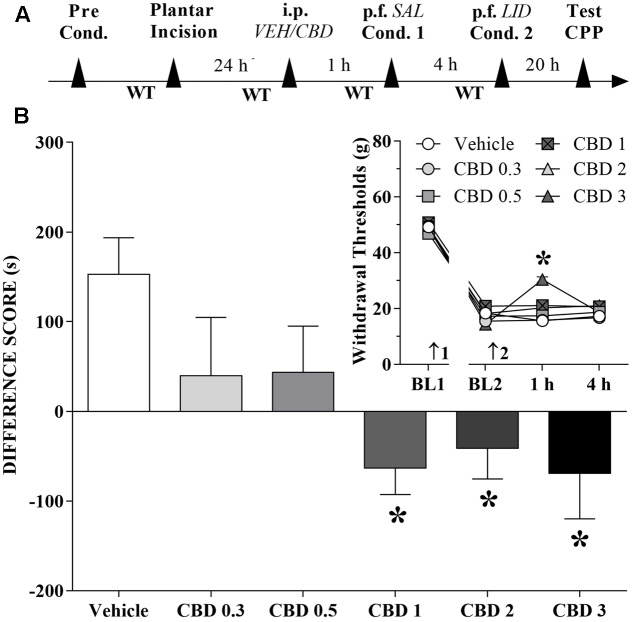

Changes Induced by Systemic CBD Injections in the CPP Produced by Peripheral Nerve Block

A time line of the protocol for the experiments is shown in Figure 2A. The motivational drive of rats with ongoing pain was assessed with the CPP paradigm. Rats that received CBD (1 to 3 mg/kg) before the first confinement did not present CPP by peripheral nerve block, but it seems that CBD itself produced CPP. The differences were statistically significant in terms of treatment [F(5,63) = 3.8; p < 0.01] according to Dunnett’s test for CBD vs. vehicle in incised rats (Figure 2B). However, incision pain-produced mechanical allodynia in these groups was reduced only by intraperitoneal administration of CBD (3 mg/kg). The differences were statistically significant in terms of time [F(3,189) = 857.6; p < 0.01], treatment [F(5,63) = 4.7; p < 0.01] and interaction time × treatment [F(15,189) = 5.4; p < 0.01] (insert of Figure 2B).

Systemic CBD Induces CPP

We investigated whether systemically administered CBD could selectively activate reward circuits in injured rats. A timeline of the protocol for the experiments is shown in Figure 3A. CBD (1 mg/kg) induced significant CPP in injured rats [F(3,42) = 6.2; p < 0.01]. CBD (0.5 mg/kg) induced no significant CPP in injured rats (not shown in Figures). CBD (1 mg/kg) did not induce CPP in sham rats (Figure 3B). One-way ANOVA with Tukey’s post hoc test demonstrated a significant effect of CBD (1 mg/kg) compared with all other groups (p < 0.05). Intraperitoneal administration of CBD (1 mg/kg) had no effect on paw WTs (insert in Figure 3B). There was a significant effect of time [F(3,126) = 254.3; p < 0.01], treatment [F(1,42) = 6.01; p < 0.01] and condition [F(1,42) = 929.0; p < 0.01] but there was no interaction between three factors. These results suggest that CBD (1 mg/kg), which is not rewarding in sham-operated rats, become rewarding in injured rats, presumably because of pain relief.